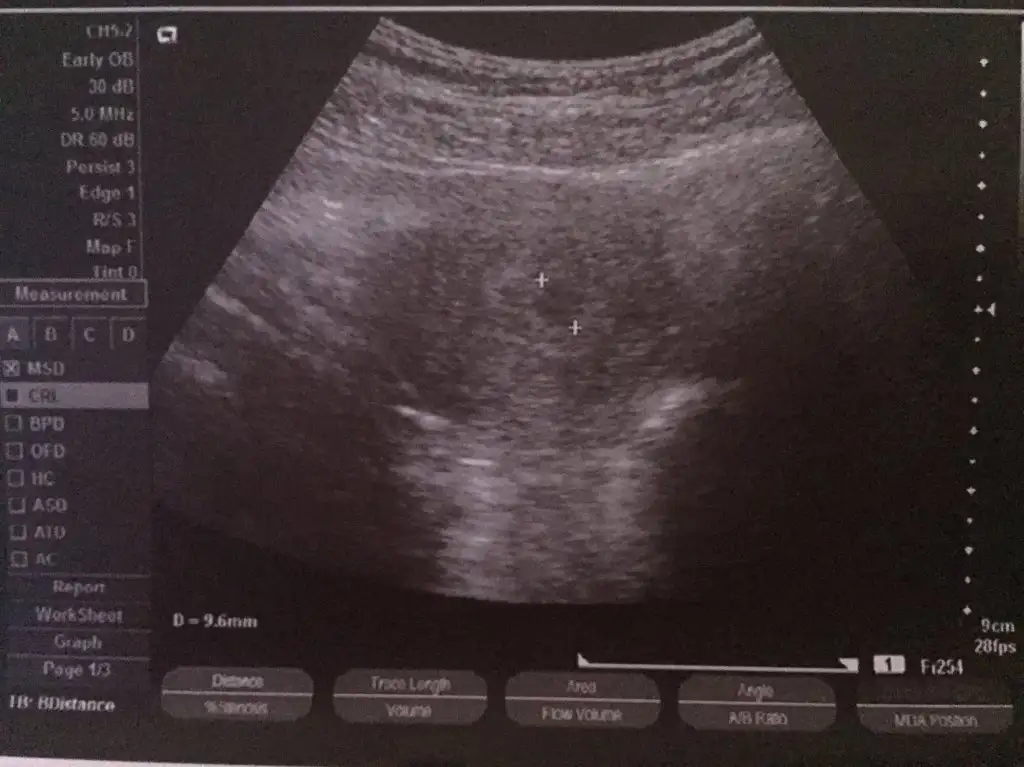

kızlarrrrrrrr :) biliyorsunuz benim sat 27 kasım. keseyi gördük :) 9.6 mm olmuş. resim de yükledim sizin için. 10 gün sonra da kalp atışlarını duymaya gidicem :)

• image.webp

32,2 KB · Görüntüleme: 153